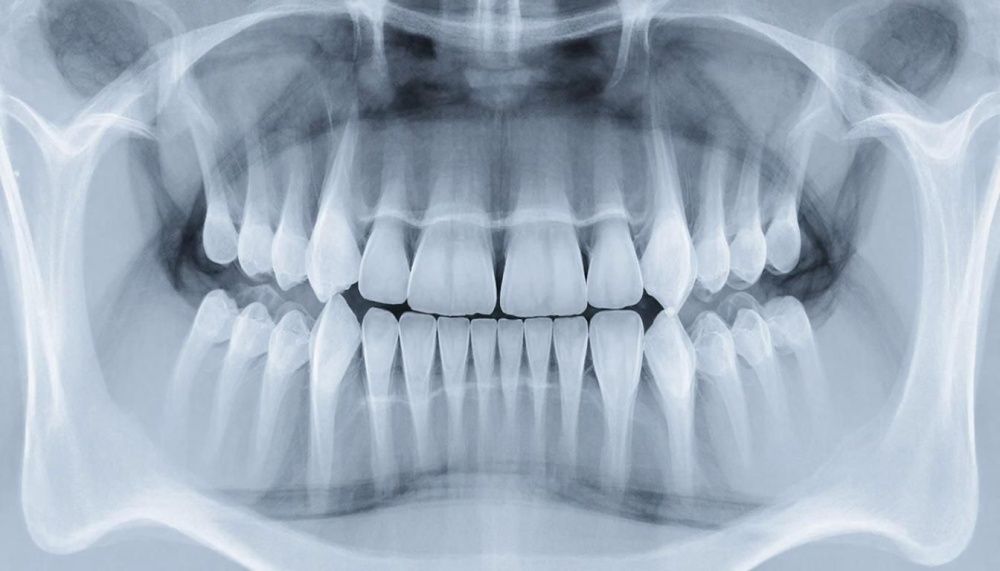

Ортопантомограмма

Панорамный снимок зубов

Общий снимок обоих зубных рядов называется панорамным. От обычного рентгеновского изображения он отличается тем, что раскрывает состояние ротовой полости панорамно и выводится на монитор компьютера. Врач имеет возможность рассмотреть проблемную зону в деталях. Он видит все, вплоть до гайморовых пазух. Ортопантомограмма показывается, если прицельного снимка для определения глубины разрушительного процесса недостаточно.

В современной стоматологии рентгеновской диагностике отводится чрезвычайно важное место. Без нее проводится лечение лишь очевидных кариозных поражений. Те негативные процессы, которые скрыты от глаз, выявляются на панорамном изображении.

Например, стоматолог без труда сможет определить развивающийся кариес под пломбой, чего нельзя сделать при обычном осмотре. Также визуально не определяется поражение на контактной плоскости зубов или последствия неправильно сросшийся носовой перегородки.

Кроме того, в отличие от плоского, панорамное изображение можно масштабировать на мониторе. Главное преимущество метода — максимальная детализация.